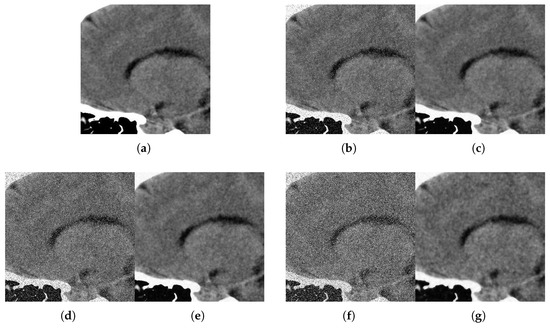

With respect to the visual appearance, by examining the denoised outputs in Figure 10, Figure 11, Figure 12 and Figure 13, we observe that the proposed filter satisfactorily preserves the details of the images and efficiently reduces the Gaussian-impulsive noise.

Figure 12. Method outputs. Sagittal view corrupted with impulsive noise p and Gaussian σ . (a) Original sagittal. (b) Noisy p = 0.1 , σ = 10 . (c) Method output. (d) Noisy p = 0.2 , σ = 20 . (e) Method output. (f) Noisy p = 0.3 , σ = 30 . (g) Method output.